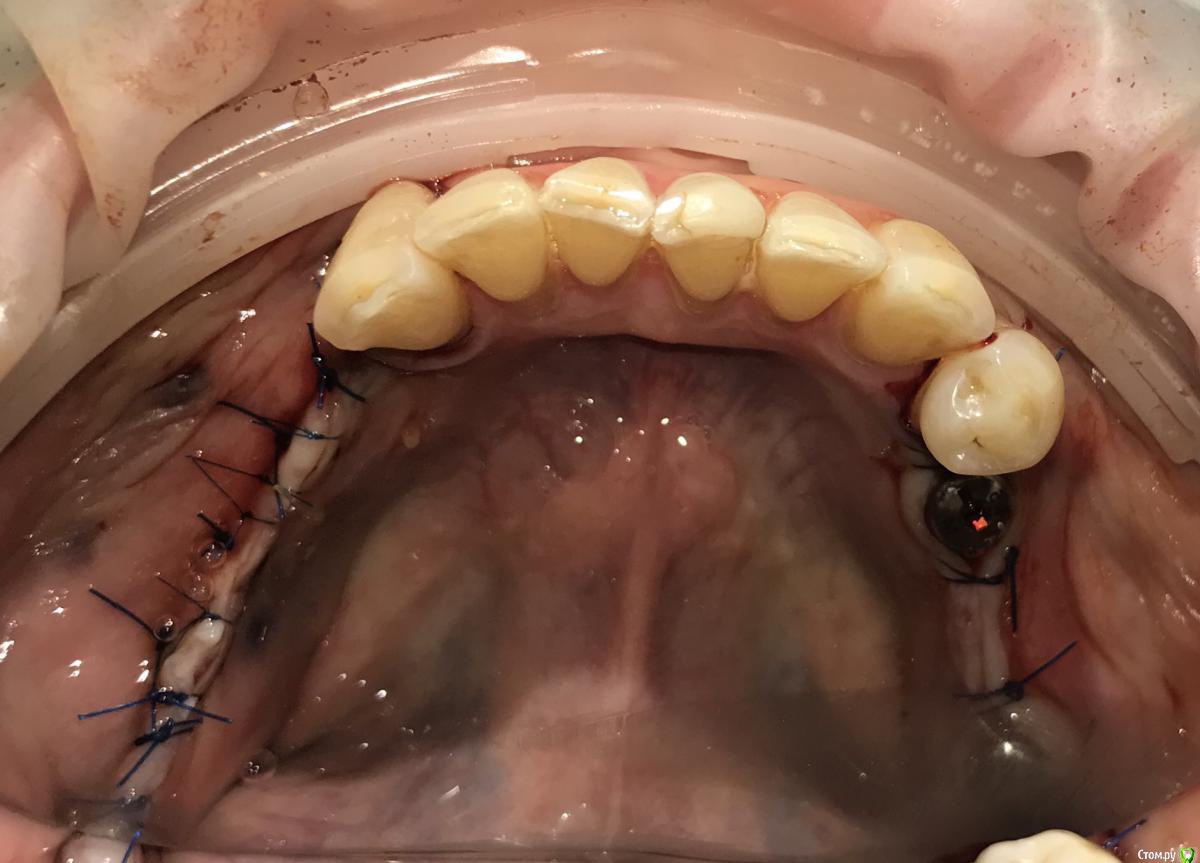

Santi Опубликовано 18 сентября, 2018 Поделиться Опубликовано 18 сентября, 2018 Имеем Концевые деффекты н/ч. Справа по плану НКР+импланты в позициях 4-6, слева импланты+ десна Итог сразу после Через 5-6 месяцев имеем такую картину Сразу после мягкотканной пластики И через пару месяцев Заранее пардоньте за качество фото и отсутствие картины ДО Ваше мнение коллеги ? 3 Ссылка на комментарий